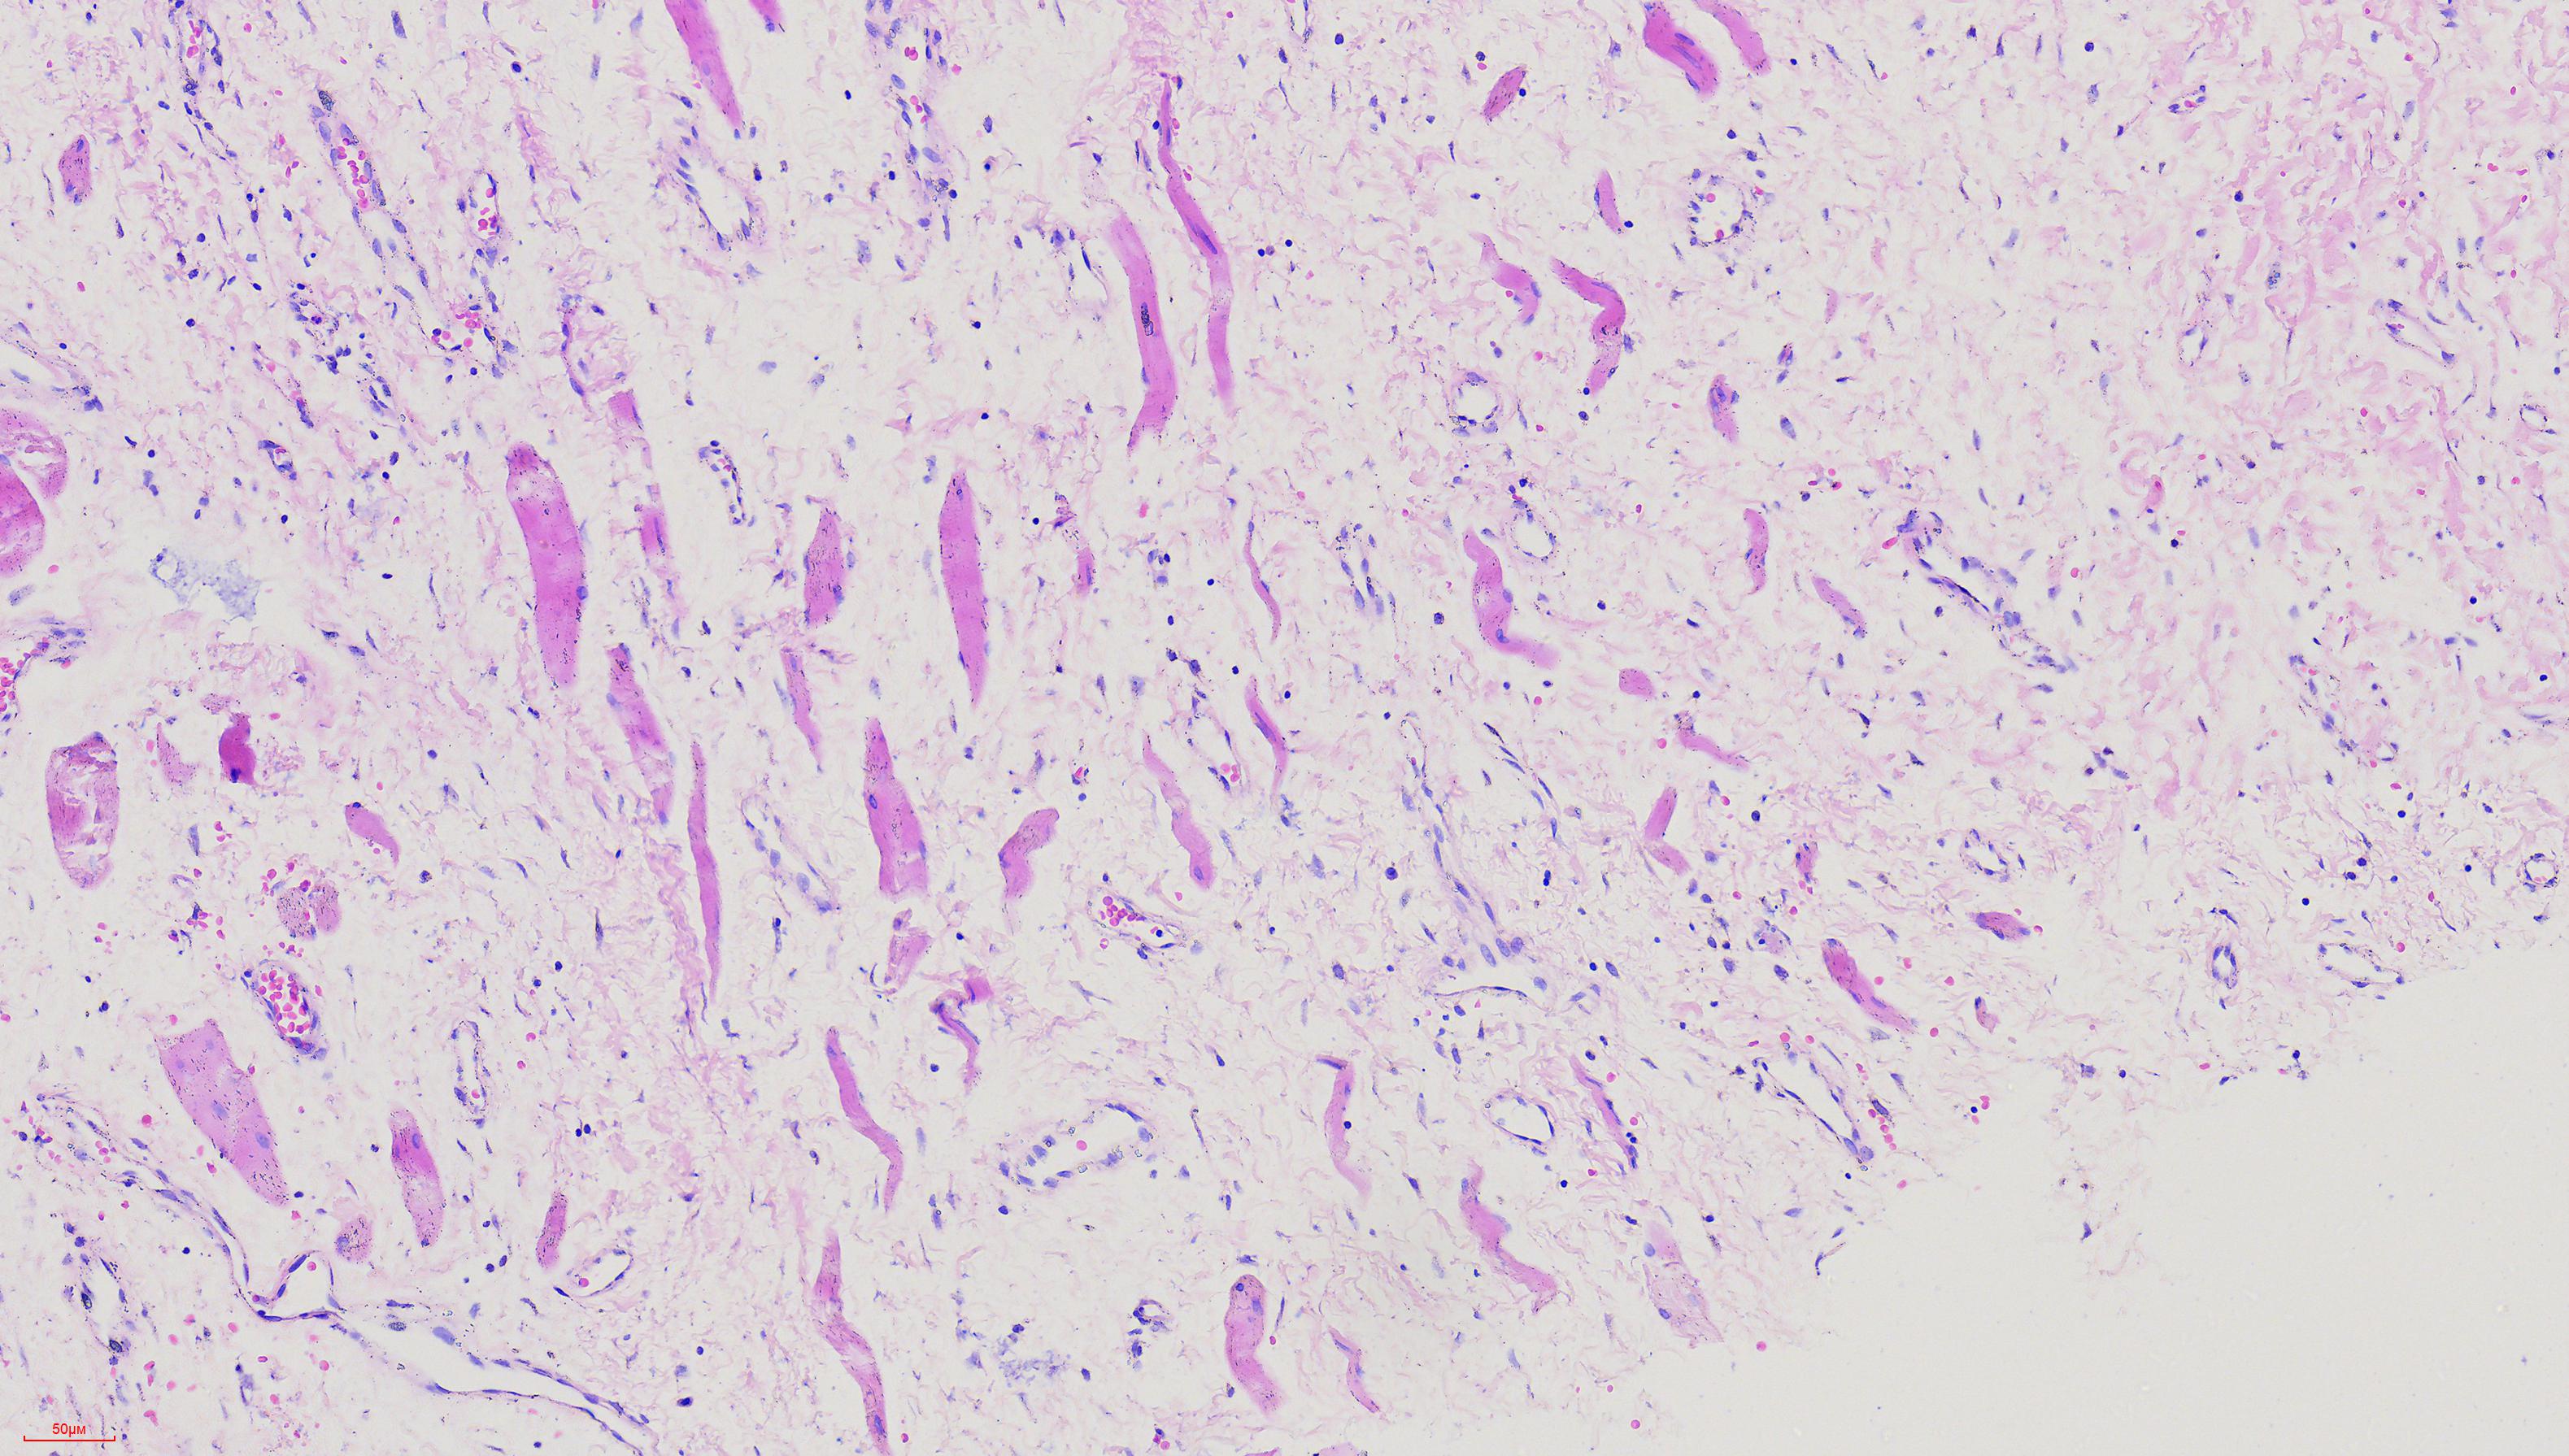

肘关节肿物

结节状组一块

图2

横纹肌、血管、纤维组织,描述诊断